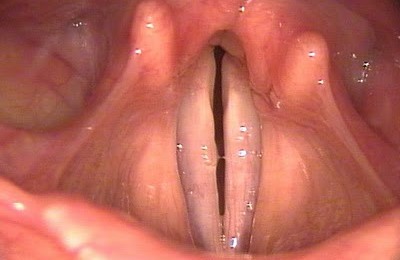

помимо этого определить гортани можно посредством использования визуального метода, то есть, осмотра.

Слизистые оболочки гортани приобретают красный цвет, характерный для протекания воспалительных процессов, значительно увеличиваются в размере миндалины.